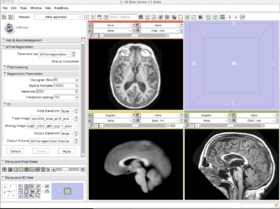

With the images loaded into Slicer, select the Registration-Affine Registration module as shown:

Set the Fixed image to icbm452_atlas_air12_sinc.hdr and the moving image to OAS1_0001_MR1_mpr-1_anon.hdr. The default settings are sufficient to register these images

With the images loaded into Slicer, select the Registration-Affine Registration module as shown:

Set the Fixed image to icbm452_atlas_air12_sinc.hdr and the moving image to OAS1_0001_MR1_mpr-1_anon.hdr. The default settings are sufficient to register these images